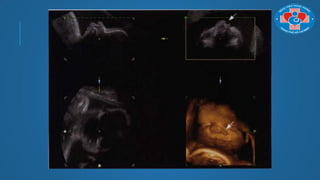

TÁI TẠO THEO MẶT PHẲNG

SIÊU ÂM TIM

TÁI TẠO THEOMẶT PHẲNG